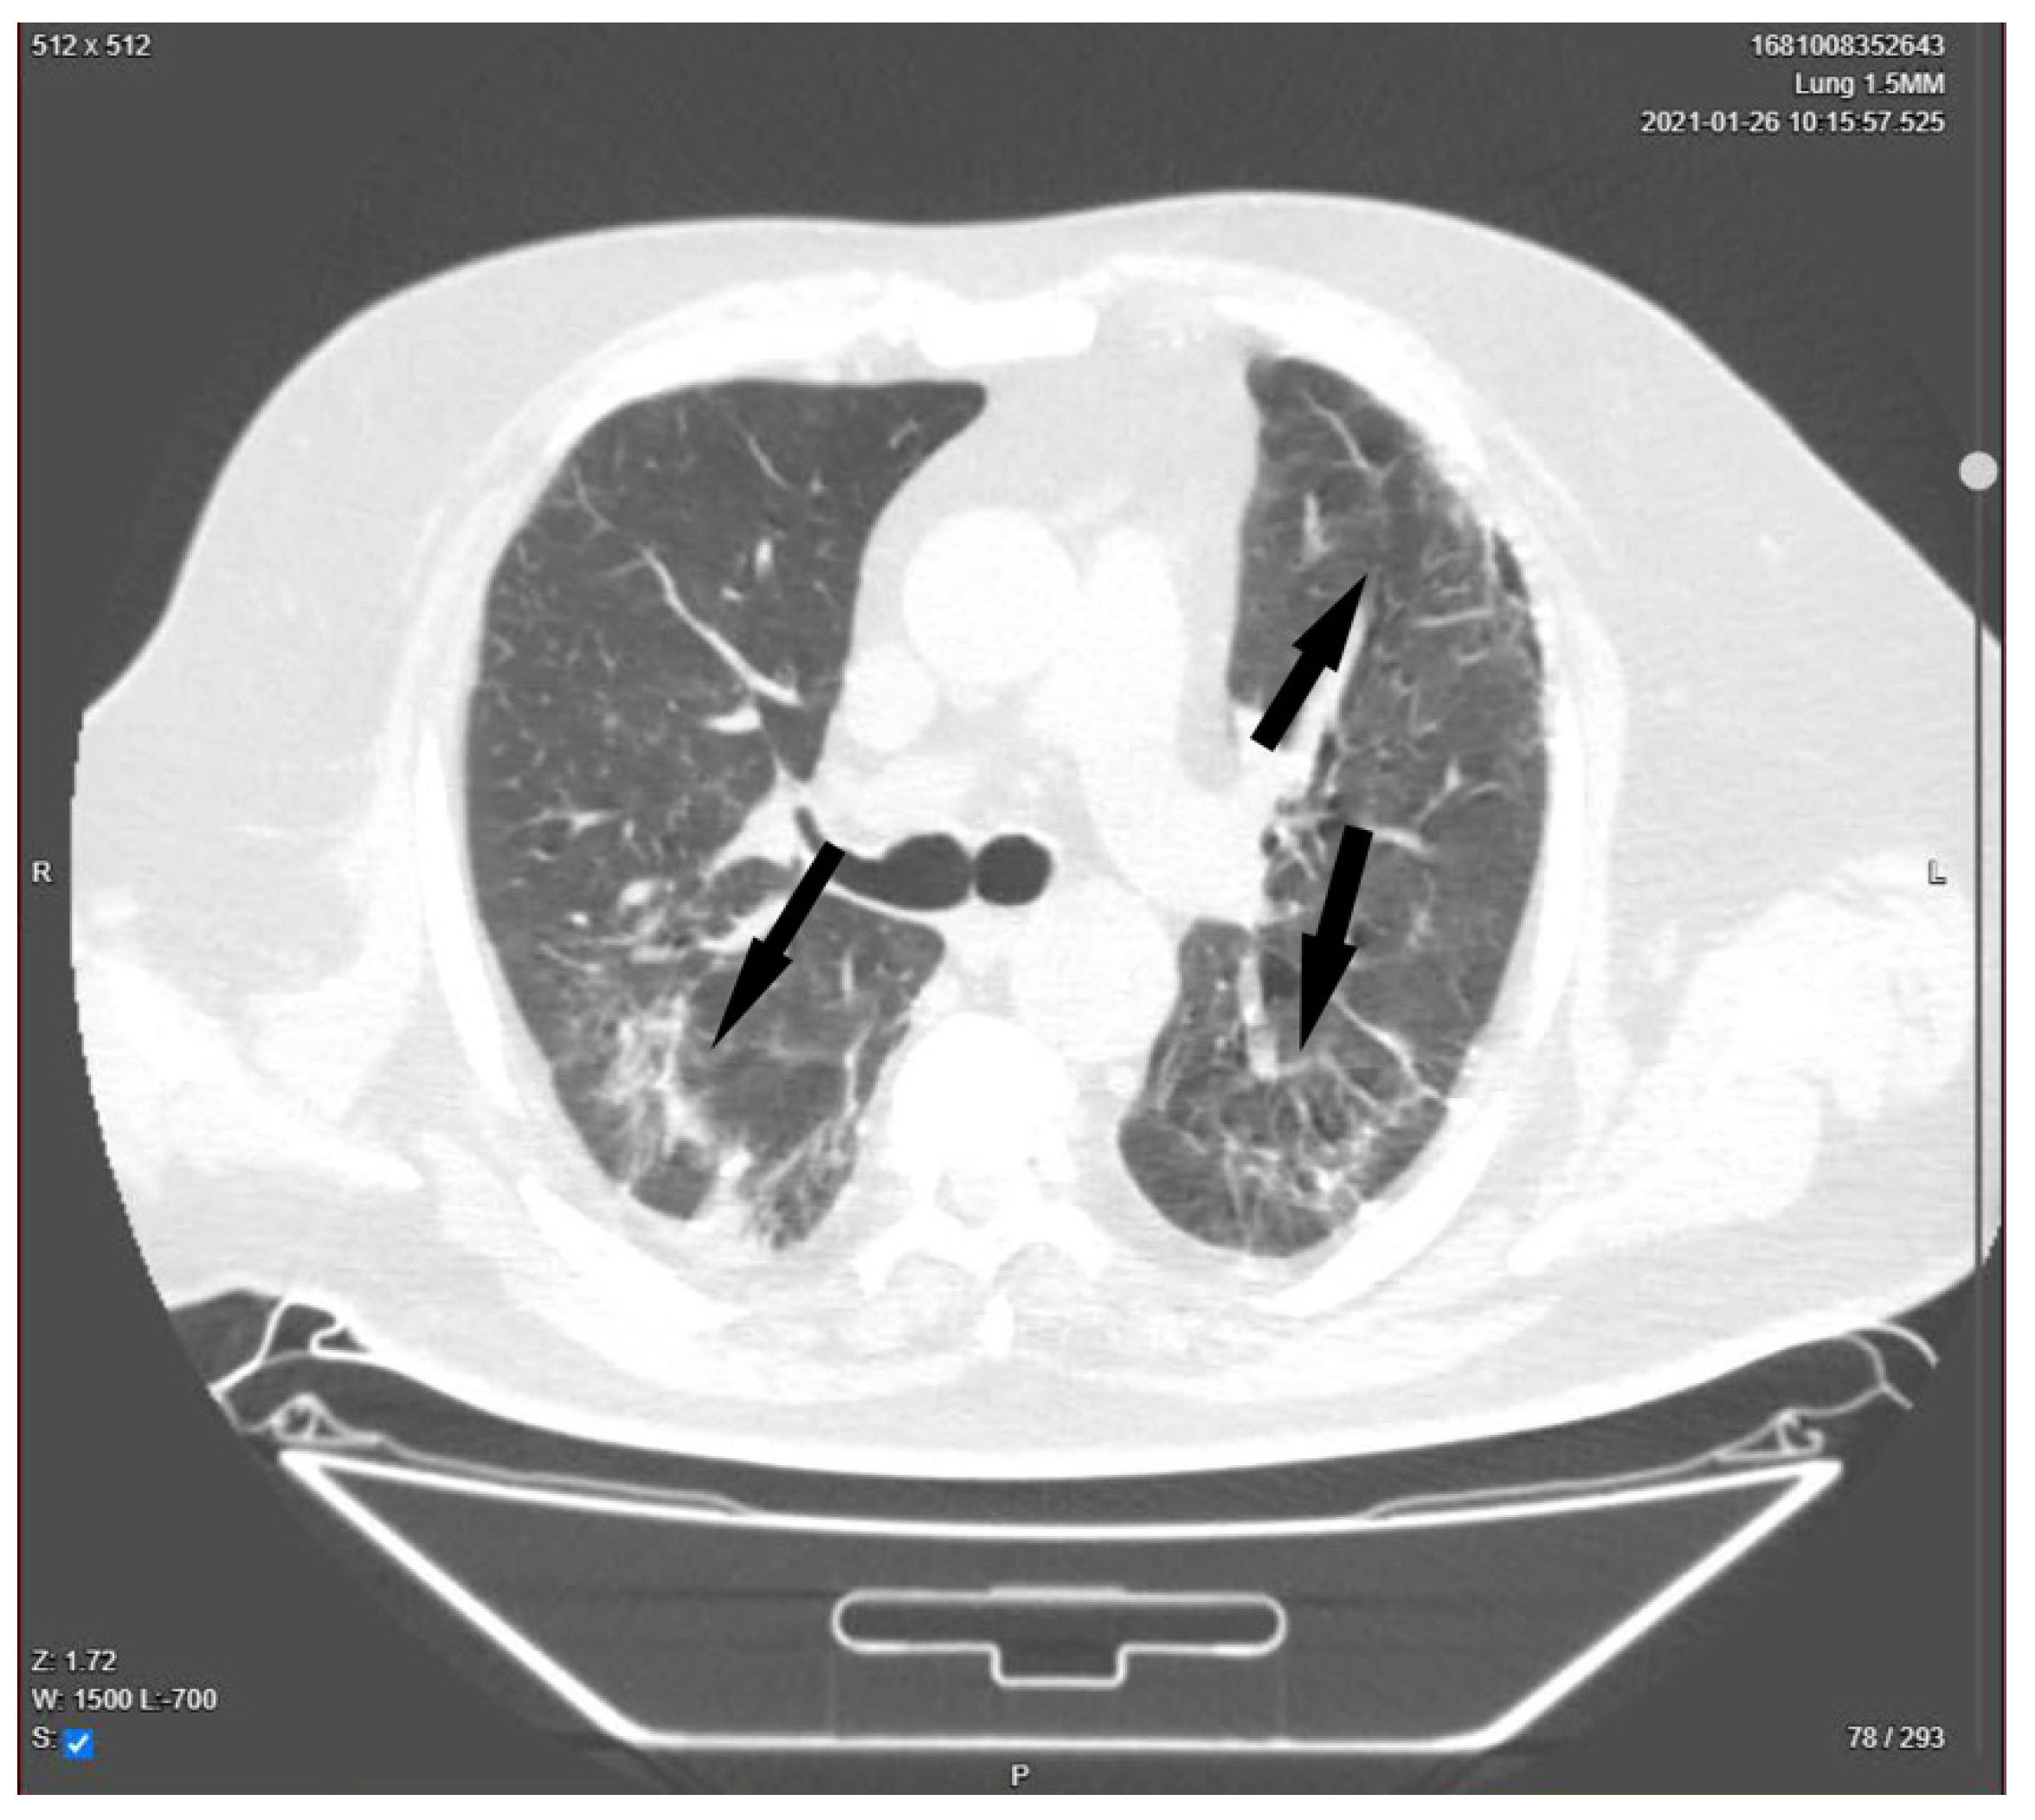

| Presentation | A 52-year-old man presented in the ER with malaise, fever, severe cough, tachypnea, tachycardia, and dyspnea, which started 2 days before the presentation. Upon rapid assessment, the patient had low oxygen saturation and showed signs of respiratory failure. The decision was made to transfer the patient to the ICU after preliminary radiological examination. |

| Day 23 | Lung CT was performed for pulmonary re-evaluation. |